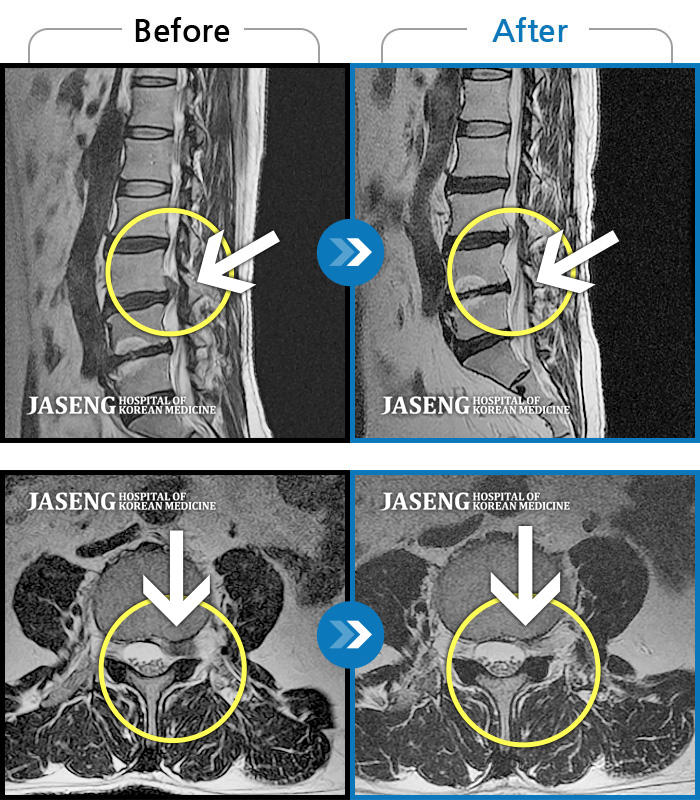

허리디스크

일산 · 김태용 원장

허리와 우측다리가 심하게 저렸다.

촬영시기

2020.05.07 ~ 2020.12.29

2021.02.26